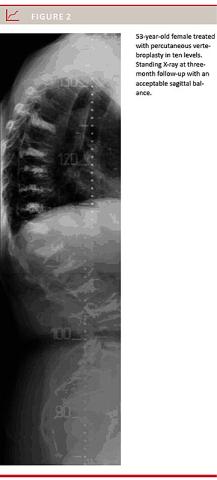

A total of 64 levels were treated between Th6 and S2. One patient received PVP in ten levels, two patients in five or six levels.